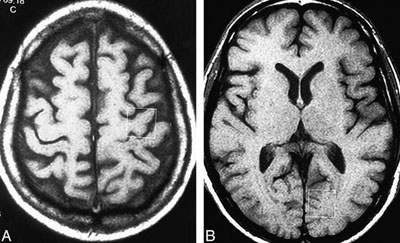

ـ اسکن MRI